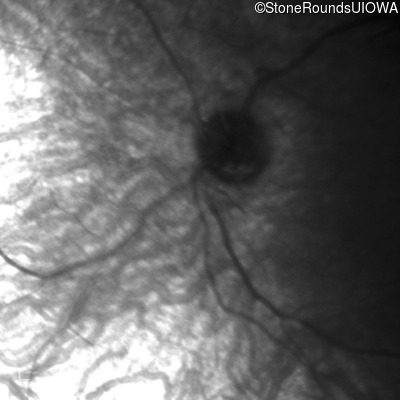

Infrared Fundus Photograph - Right -

No Light Perception

Exemplar

Expanded OCT Stack

×

Infrared Fundus Photograph - Left -

Light Perception